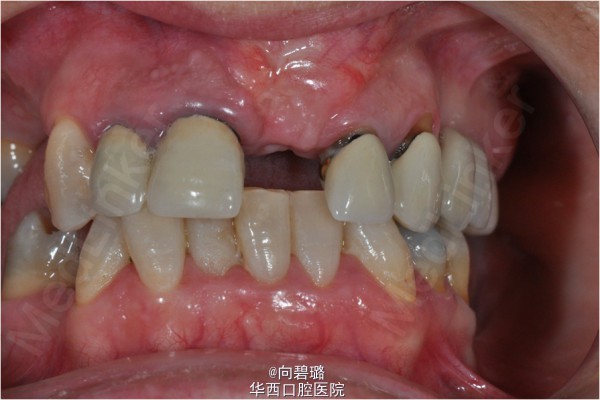

患者,女,38岁。全口多颗牙缺失。

诊断:牙列缺损 治疗计划:上颌窦外提升术。(每一颗种植体植入前,都进行了精确的共振频率分析作为种植体稳定系数的评价。)

上颌窦提升术已经成为一个世人公认有效弥补骨量减少患者的方法。自1970年以来,各种有助于骨再生的临床研究被开展,研究方面多半是关于上颌窦提升方面和囊腔填充两个方面的。本例就采用了上颌窦外提升法顺利为患者植入种植体。